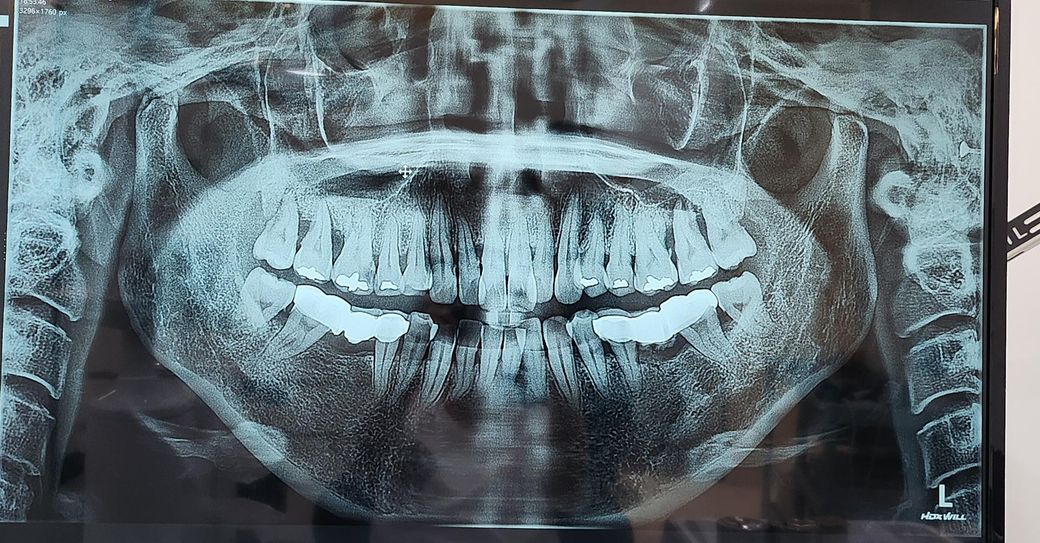

오른쪽어금니 6번 떼운데가 빠져서 통증으로치과 를방문을했는데 엑스레이를 찍은걸 보신후 떼운데빠진곳은 신경치료한후 크라운으로하고

양쪽 어금니위에 7번 치아 잇몸뼈가 녹아내려서7번8번(사랑니)발치후상악동 거상술 뼈이식 임플란트를 진행해야한다고하는데 충치가 없어도 잇몸뼈가 녹아내리면 발치후에 상악동뼈이식 임플란트를해야하는급한상황일까요?ㅠ 발치만은 하고싶지않은데 다른 치아에도 영향을 줄수있다고 하네요ㅠ스켈링.잇몸치료를 꾸준히 하고 1-2년이라도 쓰다가임플란트를 하면안되는 상황일까요ㅠ오른쪽은 발치후 당일날 상악동 뼈이식임플란트를진행한다고하는데 임플란트를 할경우 발치후3-4개월 지켜보다뼈가 차오른후에 하는걸로 알고있는데요.잇몸뼈가 안좋은데 바로 발치후에 해도되는걸까요? 다른치과에서는 왼쪽이 더안좋아서 왼쪽을 먼저 발치한후에 2-3개월 보자고하는데 어떤게 맞는걸까요?

발치 후 바로 임플란트를 할지는 각 치과의사의 전략과 능력, 진료스타일 따라 조금씩 다릅니다. 일반적으로 염증 때문에 뼈가 심하게 나아 아예 임플란트 뿌리 심어도 고정이 안되면 뼈이식만하고 좀 더 대기할 수도 있고요. 그때그때 상황에 따라 다릅니다.

일단 양쪽 위 잇몸뼈 상태가 좋지 않은 것은 분명하고, 언젠가는 발치 후 임플란트를 해야 할 처지이나 당장 막 급한 건 아닐 것 같습니다.

잇몸 염증으로 치조골이 많이 소실된거 같습니다. 발치후에 임플란트를 하셔야될것같습니다.

치조골이 내려간상태로 보이기는 합니다 통증이 없다면 염증이 없도록 관리를 하면서 사용할수 있습니다.